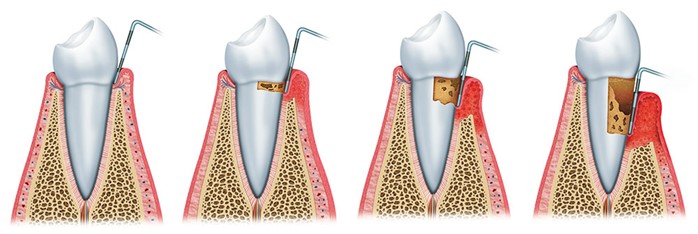

Las infecciones periodontales son un conjunto de enfermedades que, localizadas en la encía y las estructuras de soporte del diente (ligamento y hueso alveolar),están producidas por ciertas bacterias provenientes de la placa subgingival. Las bacterias anaerobias gramnegativas más importantes y prevalentes en el área subgingival son el Actinobacillus actinomycetemcomitans (Aa), Porphyro-monas gingivalis (Pg), Prevotella intermedia (Pi) y Tannerella forsythensis (Tf). Estas bacterias tienen un importante papel en el comienzo y posterior desarrollo de la periodontitis participando en la formación de la bolsa periodontal, destrucción del tejido conectivo y reabsorción del hueso alveolar a través de un mecanismo inmunopatogénico. Una vez establecida la periodontitis, se forma un infiltrado inflamatorio constituido por diferentes tipos celulares como macrófagos y linfocitos, que producirán distintos subtipos de citoquinas, mediadores biológicos responsables de la inmunopatología de diversas enfermedades.